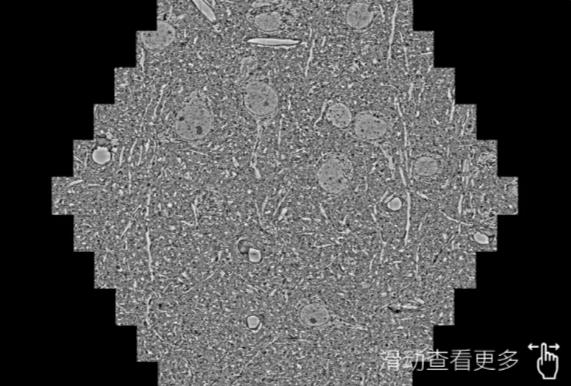

鼠脑切片。左图使用无锡蔡司无锡扫描电镜MultiSEM706对165μmx143pm面积区域成像,耗时仅需1.5秒。右图为鼠脑切片中30μm区域放大效果。样品由芝加哥大学B.Kasthuri提供。

使用蔡司高速无锡扫描电镜MultiSEM对1mm²人脑皮层组织进行高分辨成像,并对其中的各种细胞结构进行三维重构分析。左图展示了2x3mm²组织平面中锥体神经元的三维重构效果。右图显示了局部体积神经元三维重构。图像由哈佛大学chtman实验室提供,渲染图由D. Berger 制作。